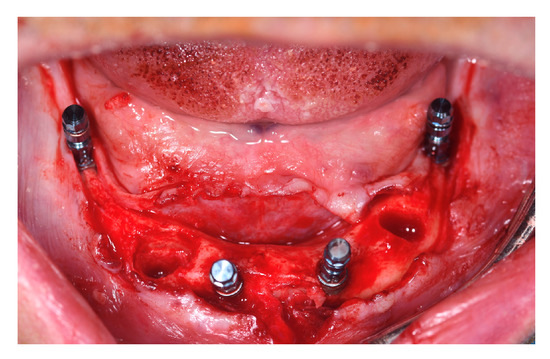

Intraoral picture of implant placement.

Implant sites for participants belonging to T1 and C were undersized, if needed, in order to reach the maximum primary stability by drilling bone, skipping the last dedicated drill in soft bone class 4. Implant placement followed the Columbus Bridge Protocol described in 2011 by Tealdo T. et al. [12]. The two distal implants were mesio-distally tilted and had a minimum length of 12 mm (Figure 4).

After implant placement, the multi-unit abutments were connected to the implants at 25 Ncm according to the following pattern:

- 0° or 17° on the anterior implants;

- 30° on the posterior tilted implant (Figure 5).

Figure 5. Abutment connection.

Flaps were sutured with interrupted resorbable sutures (4/0 Vicryl® Ethicon, Somerville, NJ, USA). In patients belonging to the T1 group, scan abutments were connected to the multi-unit abutments and a full-arch digital impression was taken using Trios 3 Shape (København K, Capital Region, 1060, Denmark). In patients belonging to the C group, pick-up transfers were connected on the platforms of the abutments and tied together with interdental floss as a frame for cyanoacrilate solidarisation (Periacryl High Viscosity® GluStich, Delta, BC, Canada) or by using flowable light curing composite (Bulkfill® Kyoto, Japan). Impressions were taken with standard plastic open trays and polyvinilsiloxane (PVS) material (Flexitime Regular and Heavy body® Kulzer, D-63450 Hanau, Germany) (Figure 6).